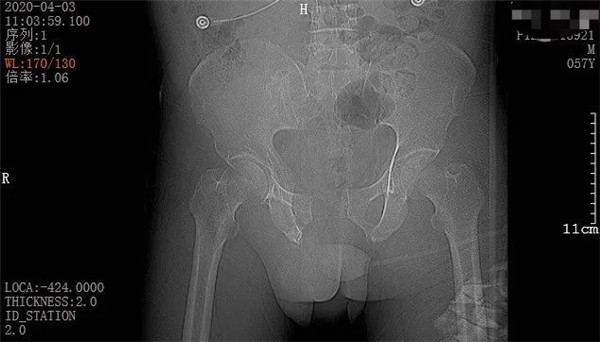

4月3日一早,和往常一樣,家住六橫的趙大叔騎著三輪車(chē)去買(mǎi)菜,誰(shuí)知經(jīng)過(guò)下坡路時(shí)剎車(chē)失靈,趙大叔重重地撞上了一根柱子后,三輪車(chē)壓倒了他身上。趙大叔頓時(shí)感覺(jué)身體疼痛不已,無(wú)法轉(zhuǎn)身、站立。在路過(guò)市民的幫助下,他迅速被送至當(dāng)?shù)蒯t(yī)院。經(jīng)CT拍攝顯示,趙大叔骨盆骨折、腹腔積血。此時(shí),大叔突然出現(xiàn)了呼吸急促、血壓不穩(wěn)定等情況,聞?dòng)嵍鴣?lái)的家屬當(dāng)即表示要到廣安醫(yī)院治療,并火速聯(lián)系車(chē)子送往我院。

CT檢查報(bào)告